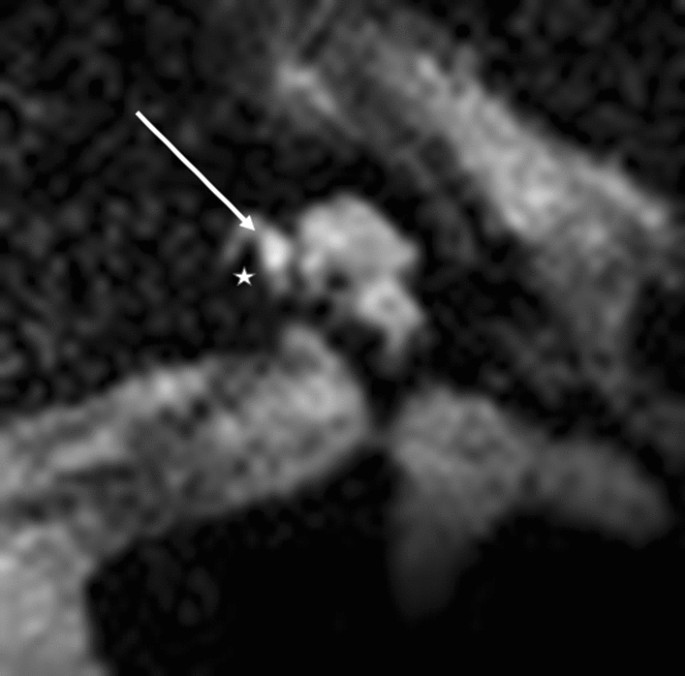

Modiolar electrode characteristics allowed us to visualize a lateral T2 signal from the electrode at the basal turn and a basilar membrane pattern (Figs. 3 and 4). This basilar membrane pattern allowed us to locate the electrode in the scala tympani definitely.

At the first turn, the estimation of the electrode position depends on the estimation of the basilar membrane and the diminishing localisation of the T2 signal by the electrode. In Fig. 5, diminishing occurred above the T2 signal and the basilar membrane signal, indicating fluid. This indicated the pattern of an electrode translocated into the scala vestibuli. Figure 7 of the same patient (No.10) confirms the irregular high position of the electrode in the first turn. In Figs. 3 and 4, the signal diminished above the electrode and the basilar membrane, indicating an electrode position in the scala tympani. Figure 6a and b are exemplary DVT of regular electrode positions at the floor of the basal and the first turn.